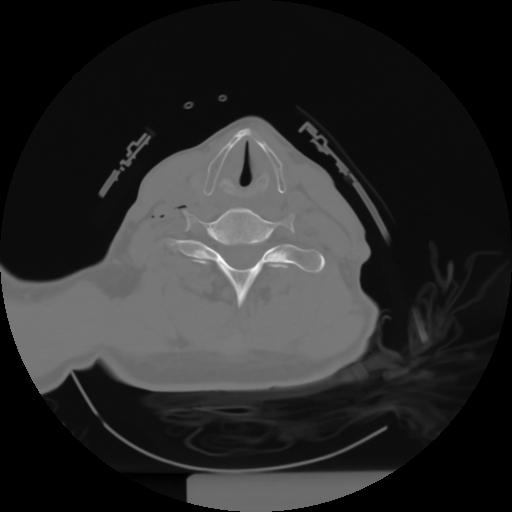

10 P.BLANDAS,,Axial,2.0,P.BLANDAS,,